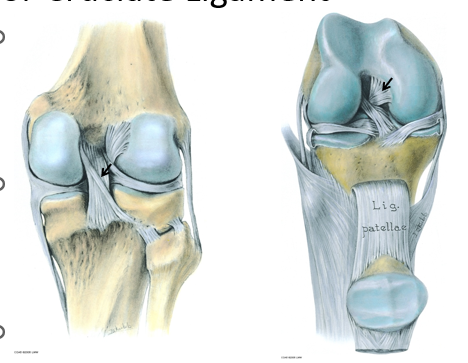

• Cruciate Ligaments

Cruciate ligaments, or parts of them, are taut in every joint position

Maintain contact between femoral and tibial articular surfaces when knee flexed

Wind around each other during medial rotation of the tibia → limited to 10°

Posterior cruciate ligament (PCL):

Prevents the femur from sliding anteriorly on the tibia, particularly when the knee is flexed

Anterior cruciate ligament (ACL):

Prevents the femur from sliding posteriorly on the tibia,  preventing hyperextension of the knee, and limits medial rotation of the femur when the foot is planted (leg is fixed

• Anterior Cruciate Ligament

Anterior intercondylar area of tibia

→ Medial side of Lateral condyle of femur

Spirals through 1100 between tibia and femur

Anteromedial band

→limits flexion

Posterolateral band

→limits extension

• Posterior Cruciate Ligament

Posterior intercondylar area of tibia

Lateral side of Medial condyle of femur

Closely aligned to centre of rotation of knee

Anterolateral band

Posteromedial band